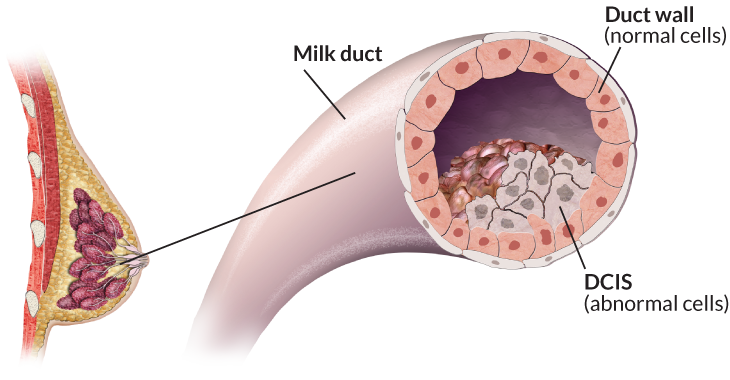

But unlike a false positive, some types of overdiagnosis can have lasting effects. Most worrisome is the detection of a problem that, left undiscovered, would never have amounted to any danger. It is “the most concerning potential harm of mammography screening,” Keating and Pace wrote in JAMA. “However, substantial uncertainty exists around its magnitude.” They put their best estimate at about 19 percent of cancers identified.